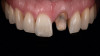

Eight weeks after the initial start of the walking bleach procedure, the final layered lithium disilicate crown was tried-in and evaluated for function and esthetics. Upon patient approval, the intaglio surface of the crown was etched for 20 seconds with a 9.6% hydrofluoric acid etchant, rinsed, and then scrubbed with a 37.5% orthophosphoric acid solution to clean out any ceramic debris. The crown was then placed into an ultrasonic bath of 91% isopropyl alcohol for 5 minutes, after which the intaglio surface was coated with silane and placed under a warm air dryer for 1 minute. A translucent self-adhesive resin cement was used to bond the final restoration to the preparation. The patients both stated that they approved of the form, function, and esthetics of the definitive restoration and that they were very pleased with the final results (Figure 13 through Figure 18). Routine periodic evaluations and radiographs were scheduled to monitor their oral health and esthetics.

(14.) Case 1: Right- and left-side profile views of the definitive all-ceramic restoration on the maxillary right central incisor.

Figure 14

(15.) Case 1: Right- and left-side profile views of the definitive all-ceramic restoration on the maxillary right central incisor.

Figure 15